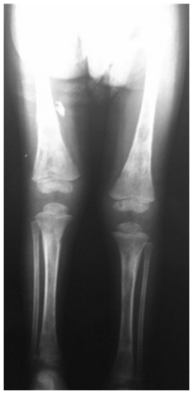

At abdominal ultrasonography, it was noted heterogeneous image, irregular, ill-defined, with Doppler vascularity in the right hepatic lobe (Figure 2). It is also visualized, at the right adrenal region a rounded image of imprecise limits, predominantly hypoechoic, with calcifications and Doppler vascularization, measuring about 3.7x2.1 cm in its largest axis (Figure 3).

Figure 2 Abdominal ultrasound demonstrates in the right hepatic lobe, a heterogeneous and ill-defined image, diffuse vascularized at the Doppler study.